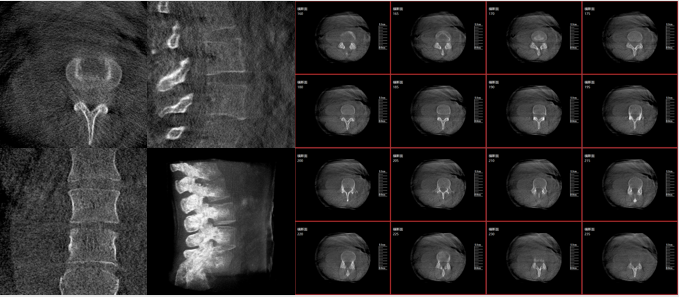

從下圖中可以看到二維影像能夠提供目標(biāo)區(qū)域在某一個(gè)平面的重疊影像,雖然因?yàn)槿梭w不同組織的密度差異,使得圖像具有較為豐富的信息量,但組織間的相互重疊還是會(huì)出現(xiàn),諸如空間位置等眾多信息在影像中遺失或不可辨認(rèn)的情況,影響了醫(yī)生對(duì)信息的收集與應(yīng)用。

術(shù)中二維影像

而三維影像的MPR圖像組可以通過(guò)不同平面的切分,使成像區(qū)內(nèi)更豐富的信息得以呈現(xiàn)。尤其是二維影像無(wú)法涉及的橫斷面,提供了另一個(gè)空間維度的信息量。

術(shù)中三維C臂影像